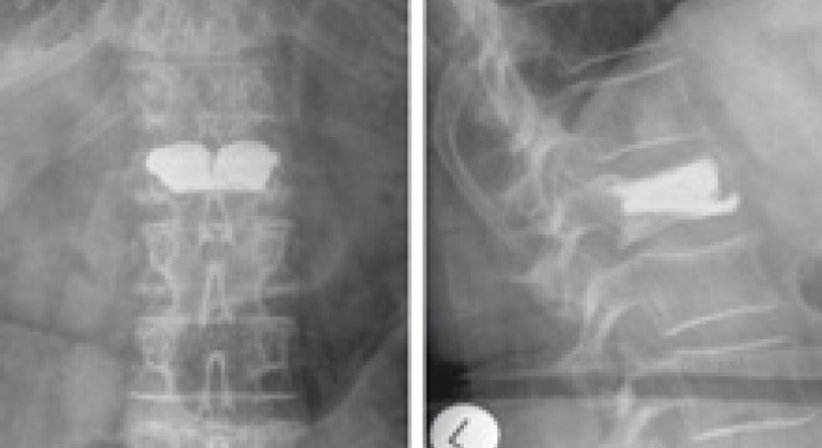

• Minimalinvasive Wirbelkörperaufrichtung vonFrakturen bei Osteoporose (Ballonkyphoplastie): Dieser Eingriff kann in der Regel sogar ambulant durchgeführt werden!